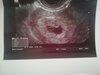

Witam, według badania USG jestem w 6 tygodniu (według danych z okresu powinnam być w 7). Jest zarodek pecherzyk ale nie widać akcji serca, czy jest jakaś szansa :( jak dobrze odczytuje wynik to pecherzyk ma 0,41 a zarodek 0,72.

Na zdjęciu USG widać że pisze7tydzien 4dzien,więc powinno ci się zgadzać,Miałaś USG dopochwowe?Bo czasem ciężko zauważyć bicie serca.Moj ginekolog nieźle się nakręcił żeby uchwycić serduszko.A co powiedział twój lekarz?